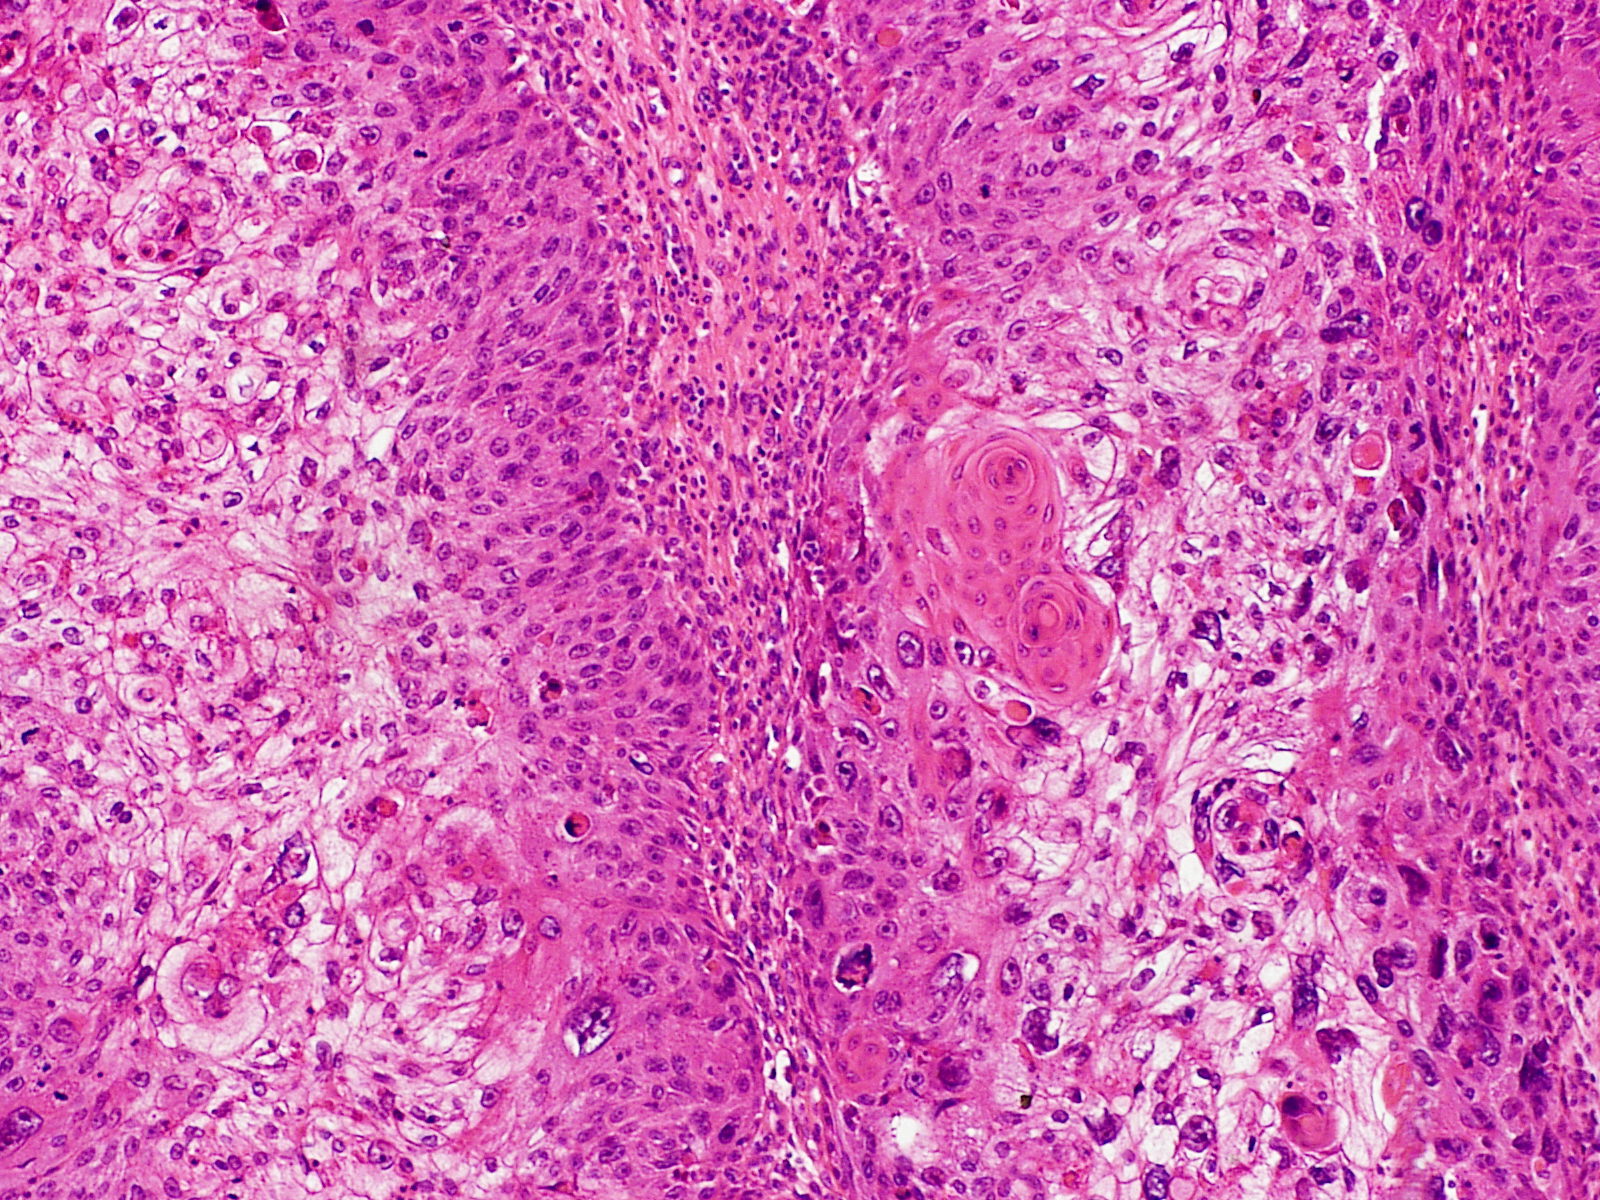

편평상피세포암(SCC)은 상피 계통의 암 줄기 세포가 반복적이고 제어되지 않게 분열하면서 시작된다.[19][20][21] 이 암은 신체 여러 부위를 덮고 있는 편평한 세포인 편평 상피 세포에서 발생하며, 그 중 일부는 각질 세포이다. 암세포가 축적되면 비정상 세포의 미세한 초점이 생기는데, 초기에는 기원 세포가 있던 조직 내에 국한된다. 이러한 상태를 편평상피세포 상피내암종이라고 한다.

병변이 성장하여 인접 구조를 파괴하고 침투하면 "침윤성" 편평상피세포암이라고 한다. 침윤성 암은 다른 장기로 퍼져 전이를 일으킬 수 있다.

병력, 신체 검사 및 의학 영상은 편평상피세포암을 시사할 수 있지만, 일반적으로 조직병리학적 생검을 통해 진단을 확정한다. TP63 염색은 편평상피세포암의 주요 조직학적 표지자이다. 또한 TP63은 편평 세포의 정체성을 확립하는 데 필수적인 전사 인자이다.[18]